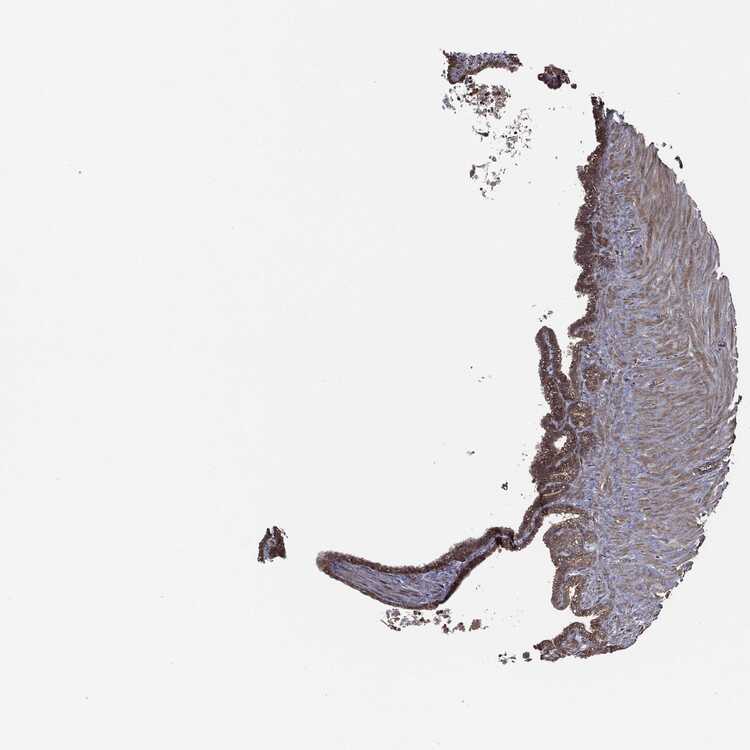

SEMINAL VESICLE - Antibody stainingi

Antibody staining in the annotated cell types in the current human tissue is reported as not detected, low, medium, or high, based on conventional immunohistochemistry profiling in selected tissues. This score is based on the combination of the staining intensity and fraction of stained cells.

Each image is clickable and will lead to virtual microscopy that enables deeper exploration of all samples and also displays staining intensity scores, fraction scores and subcellular localization as well as patient and tissue information for each sample.

Antibody HPA048606Antibody HPA059863

Glandular cells MediumHigh